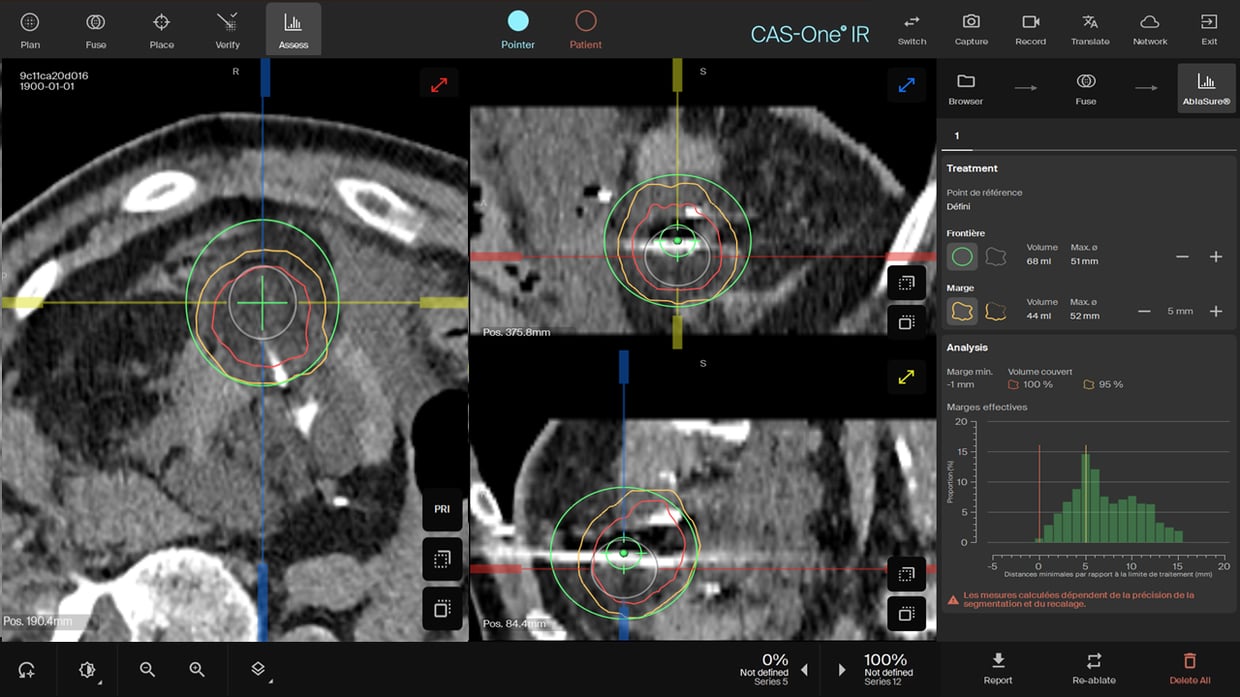

AblaSure showing full coverage after the 2nd freezing cycle.

- AblaSure® showed a complete coverage after the 2nd freeze cycle and also confirmed post thawing and retrieval of the needles.